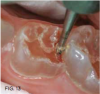

Case 4. At his first dentistry appointment, a 5-year-old with dentinogenesis imperfecta had large caries lesions on the distal of both mandibular primary first molars (Figure 12), along with smaller caries lesions on the distal of the maxillary right primary canine tooth and distal surface of the maxillary right first molar. The distal marginal ridge of the mandibular left second primary molar was fractured and subsequently trimmed smooth, but there was no caries detected in the exposed dentin. Stainless steel crown restoration of the primary first molars would have been difficult to accomplish because of the anatomical form of those teeth, the amount of wear/erosion of the maxillary first molars, and severity of carious destruction of the mandibular first molars. It was predicted that those teeth would be lost to extractions prior to their normal exfoliation time, therefore the goal was to preserve the teeth in place until eruption of the permanent molars to facilitate eventual space maintenance planning. It was thought that SDF could provide an immediate interim solution for caries control for this child, and after this was explained, the boy's father agreed to that treatment immediately at that visit. With cotton roll isolation, top layers of carious tooth substance were debrided from the mandibular first molars using a slow-speed round bur (Figure 13). No anesthetic injections were needed, and the patient related no discomfort. SDF was then painted on the caries lesions of the four teeth (Figure 14), followed by fluoride varnish application (Figure 15). The patient was seen several weeks later for renewed SDF application and dental prophylaxis (Figure 16 and Figure 17).

Fig 13. A layer of carious tooth substance debrided painlessly.

Fig 13

Fig 14. SDF applied.

Fig 14